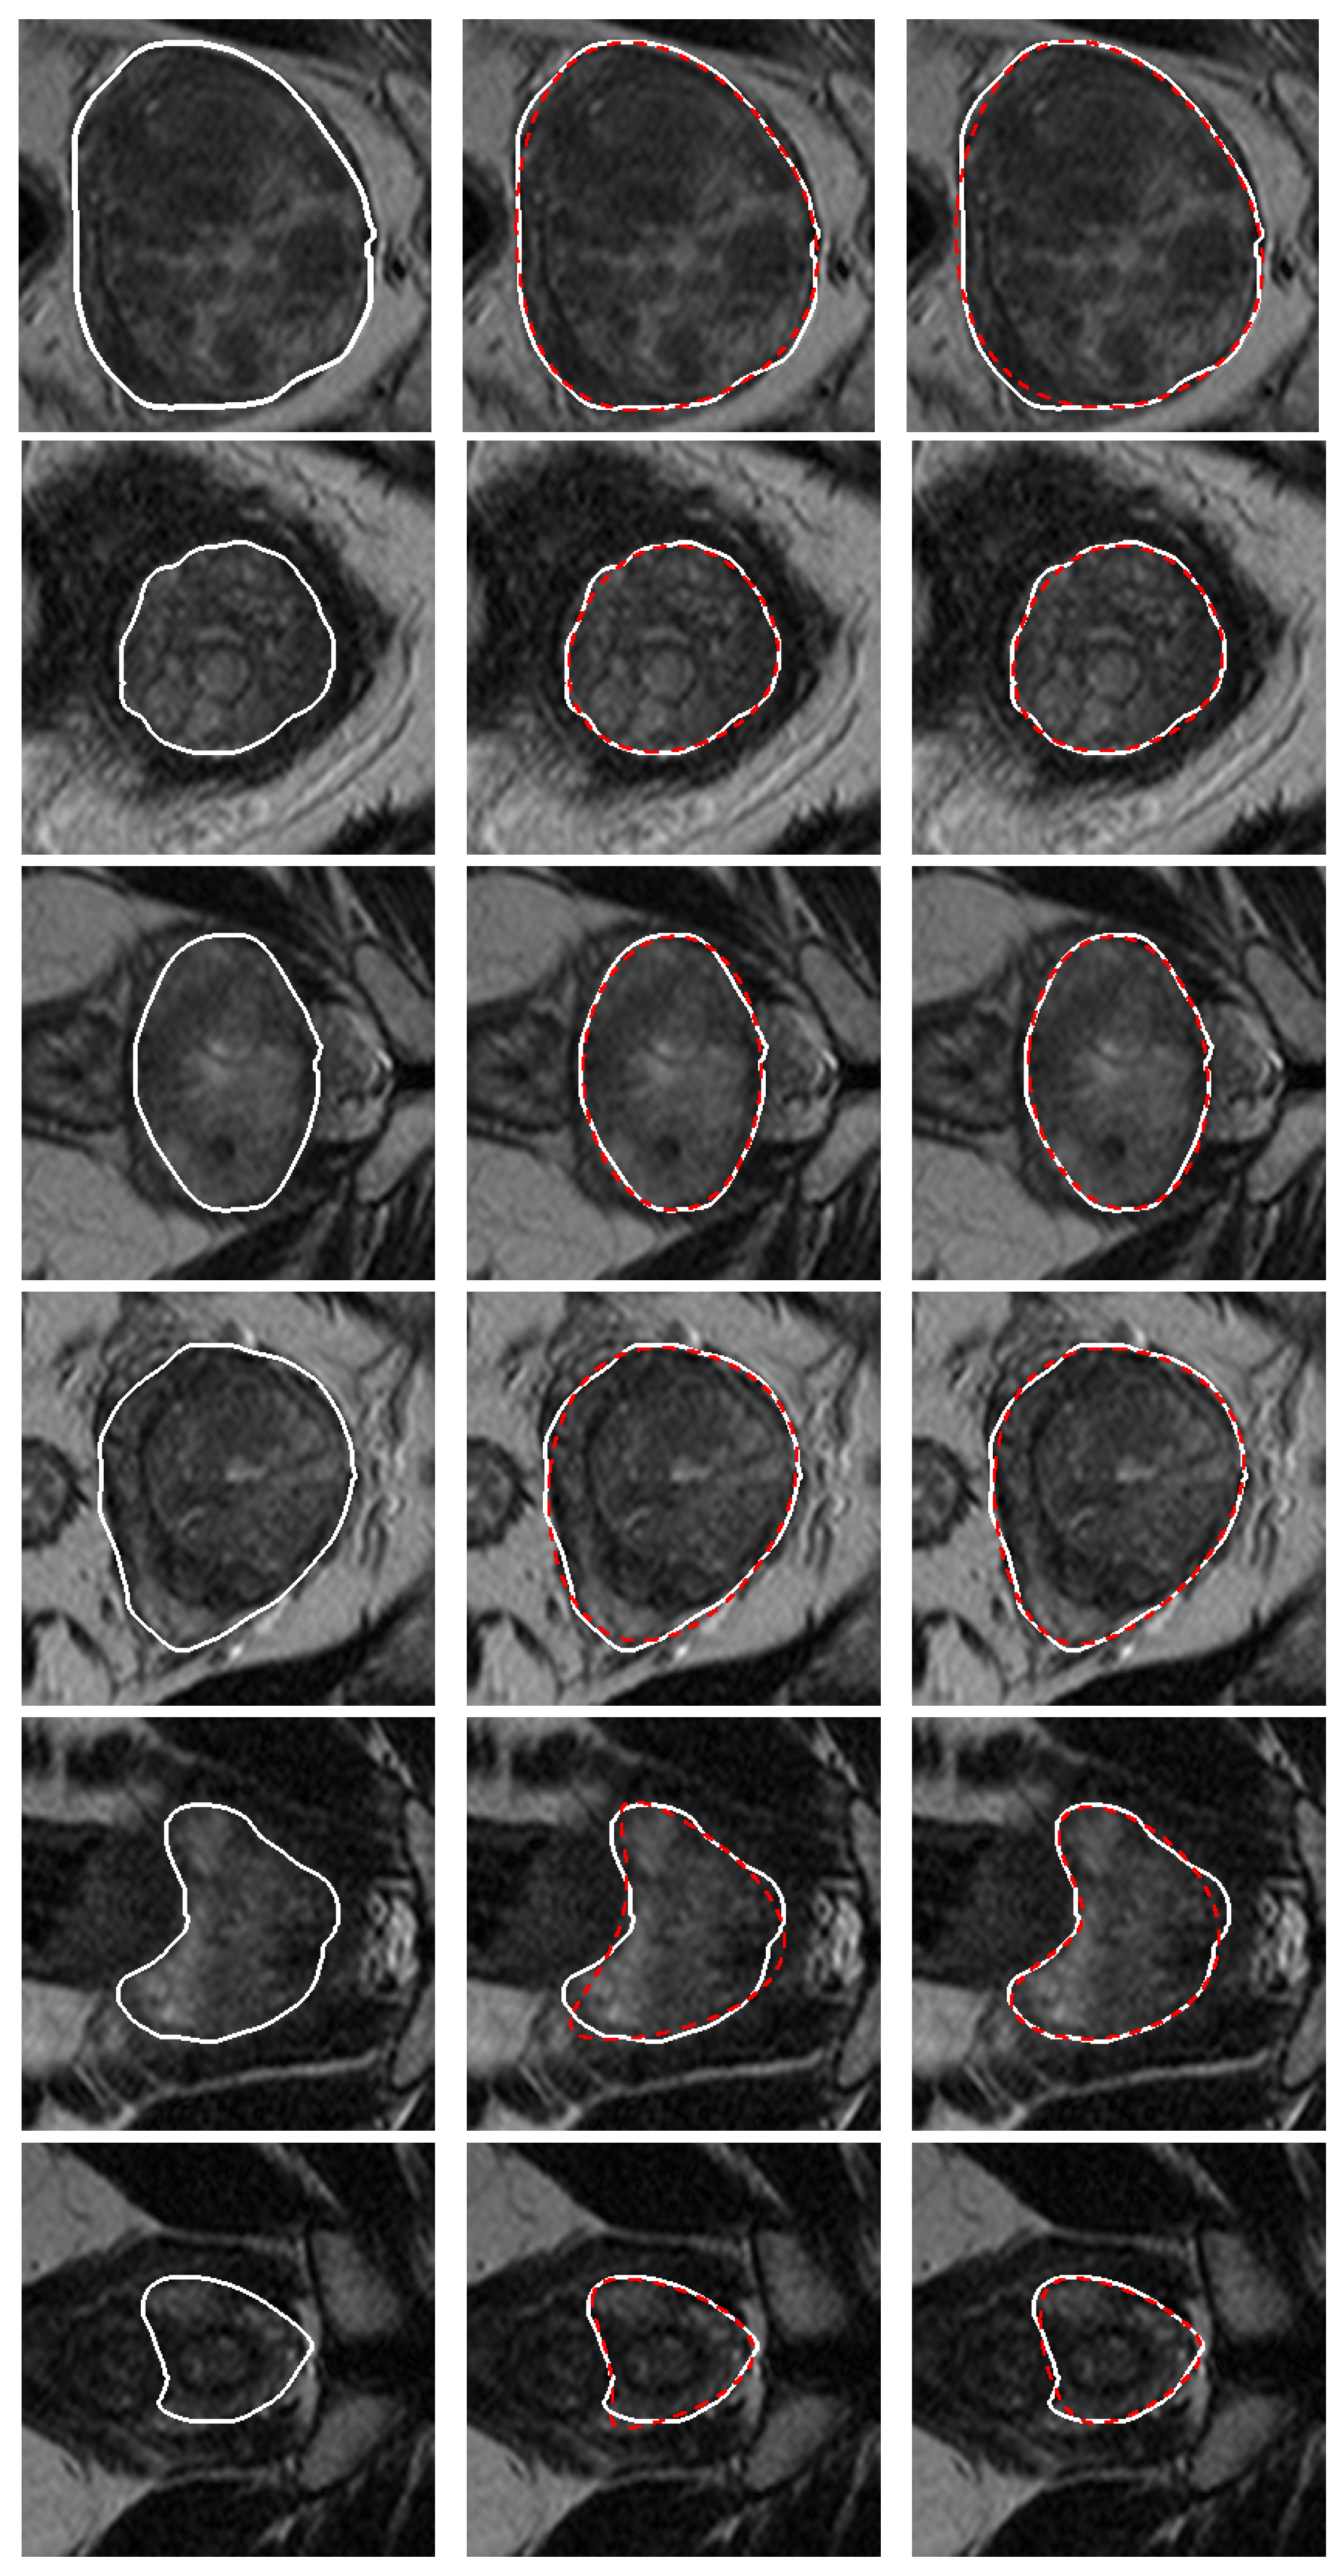

3. Validation of the Models

4. Results and Discussion